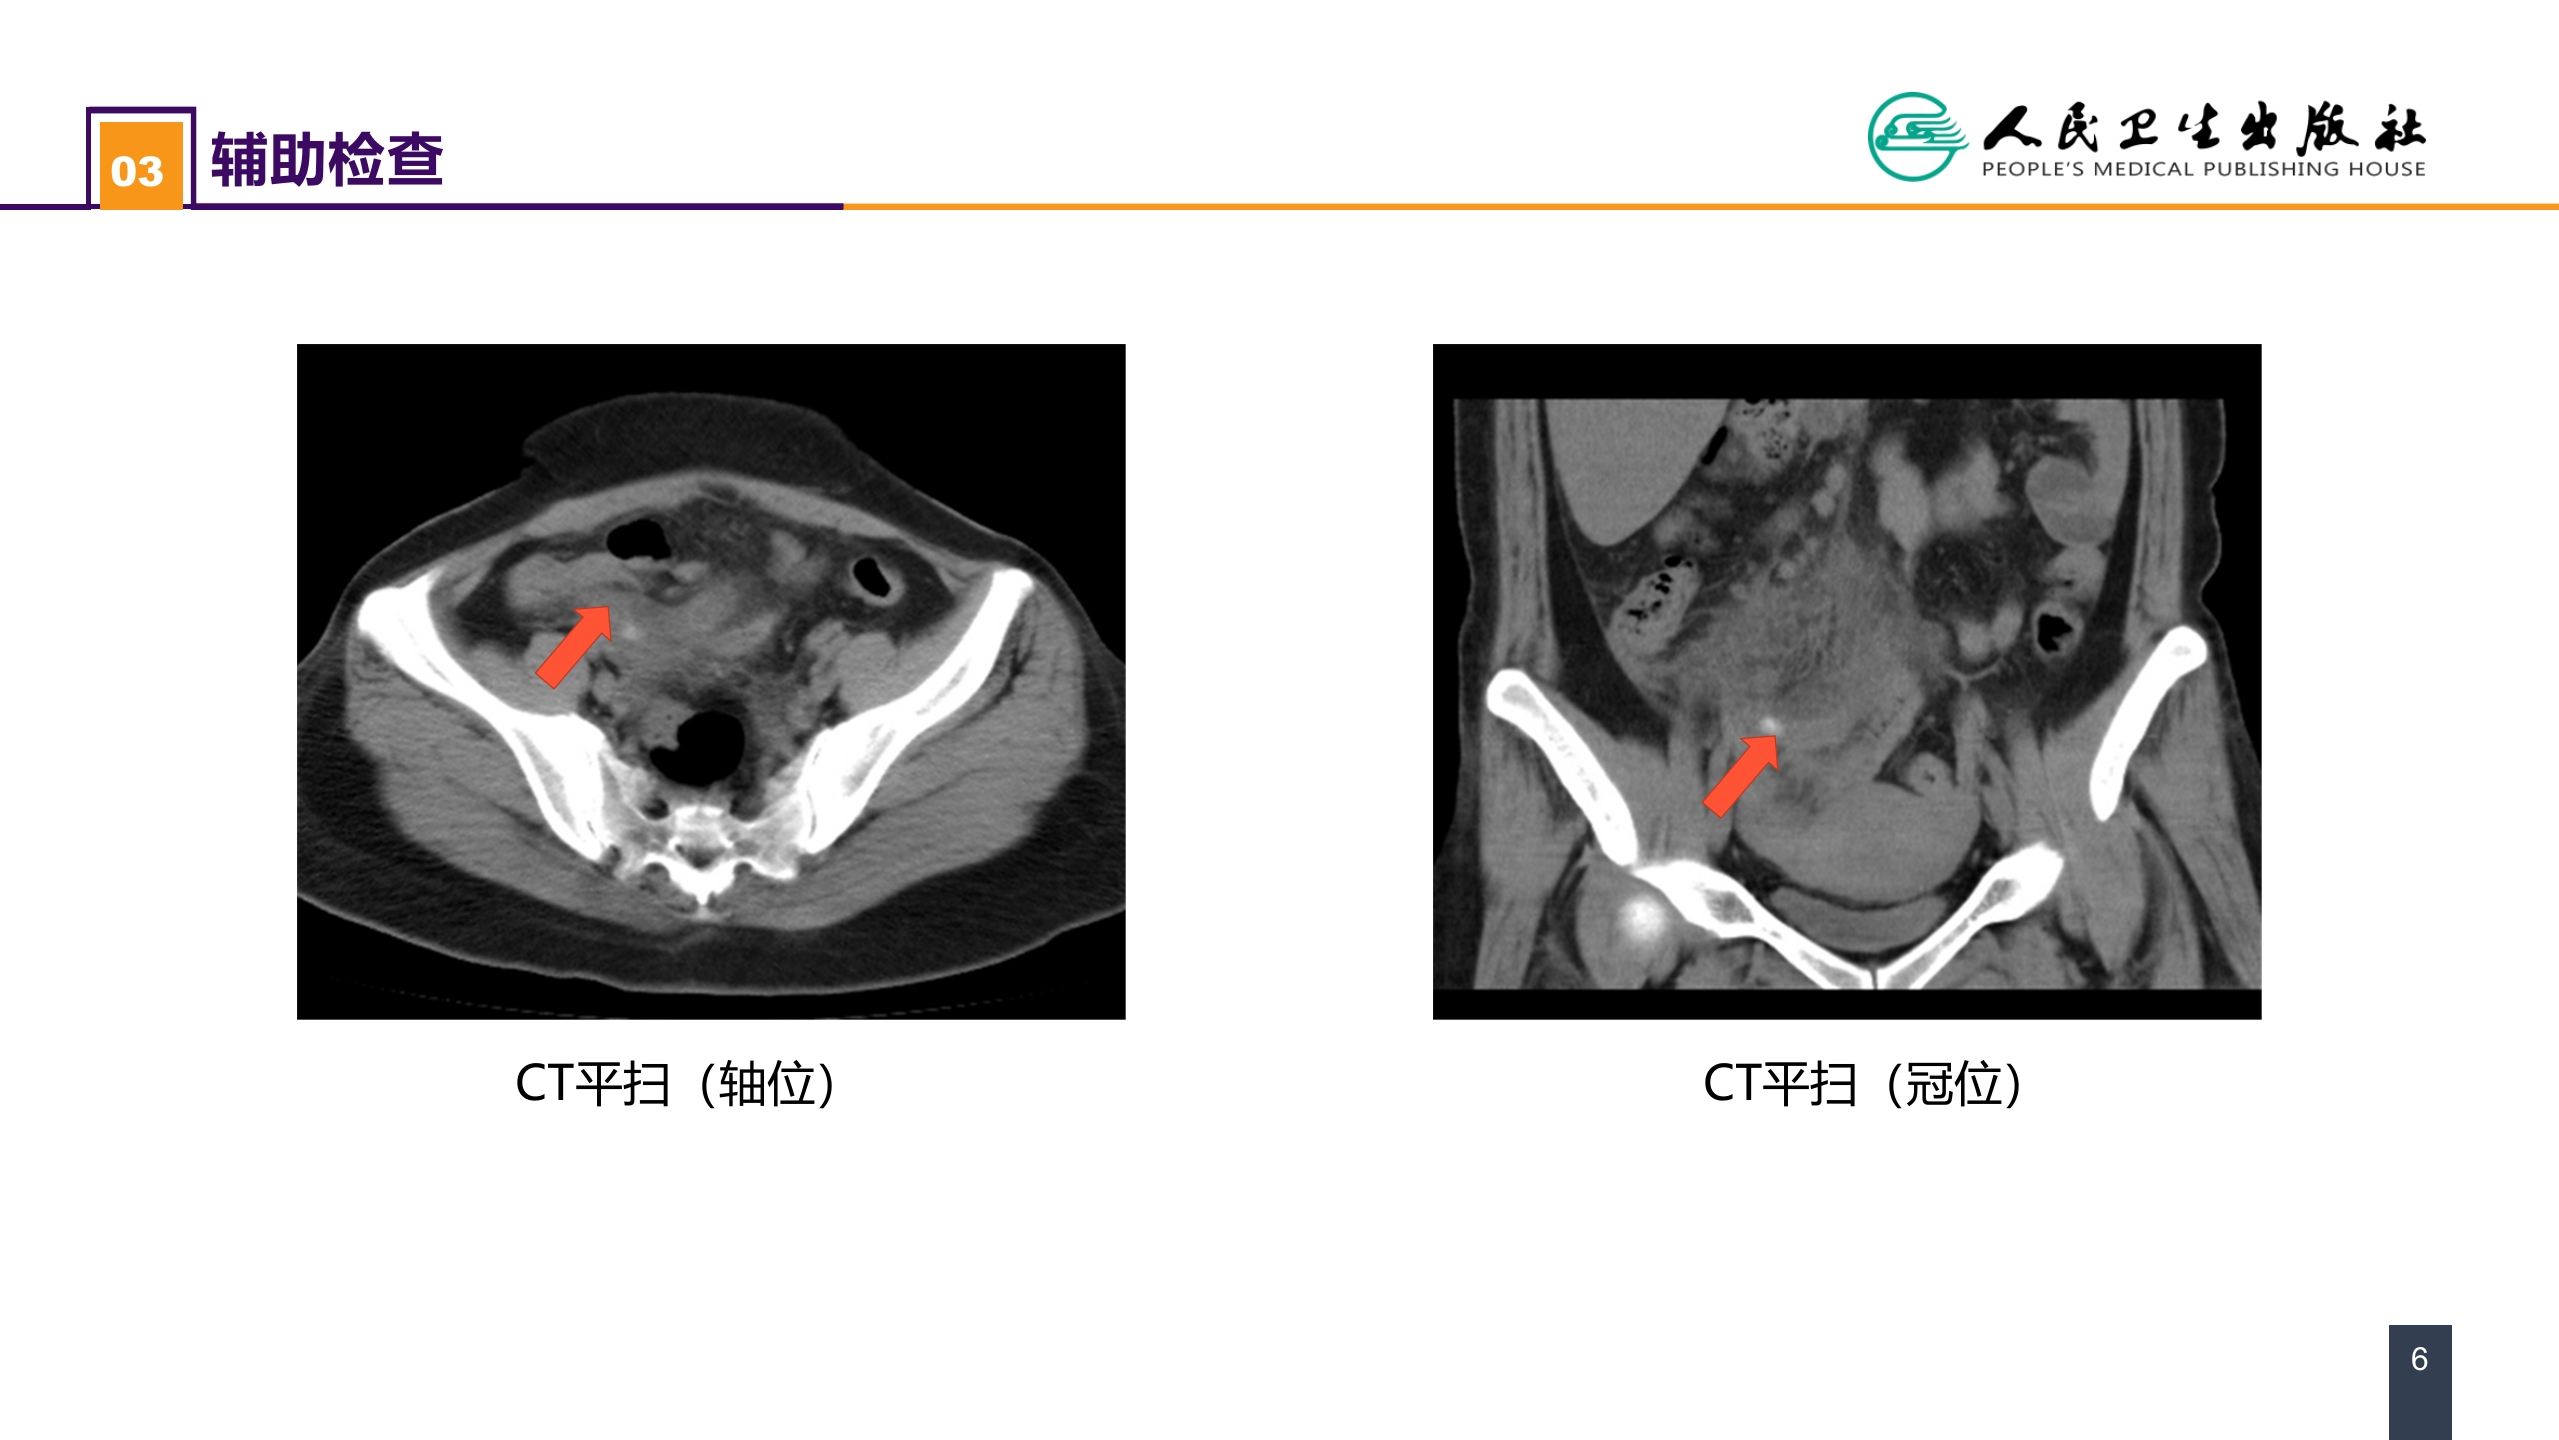

第三十六章 阑尾疾病 案例分析-急性化脓性阑尾炎